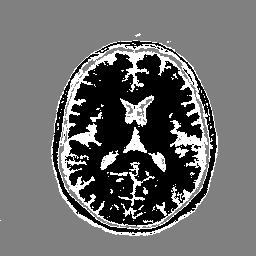

Figure 5 displays results obtained with the CNC, ATCG-TV, Chan & Vese, and LR-CNC algorithms for Gaussian noise level L=0.3L=0.3. These tests are applied to the MRI image with the cluster number set to K=3K=3, and to a Millennium simulation 222https://wwwmpa.mpa-garching.mpg.de/galform/virgo/millennium/ with cluster number K=2K=2.

Refer to caption Refer to caption Refer to caption Refer to caption Refer to caption Refer to caption

Original Observed Chan &\& Vese ATCG-TV CNC LR-CNC

Fig. 5: Segmented MRI and Millenium images for Gaussian noise with L=0.3L=0.3, and for K=3K=3 and K=2K=2, respectively.

Table 3 shows PSNR and SSIM values for segmented images determined by the CNC, ATCG-TV, Chan & Vese, and LR-CNC algorithms for several Gaussian noise levels LL when applied to the MRI and Millennium images. Figures 6 and 7 display the relative differences (38) and PSNR-values of images determined at each iteration of the CNC, ATCG-TV, and LR-CNC algorithms as functions of the iteration number when these algorithms are applied to the MRI and Millennium images. The Gaussian noise level is L=0.3L=0.3 and we seek to determine K=3K=3 and K=2K=2 clusters in the MRI and Millenium images, respectively.

method CNC ATCG-TV Chan &\& Vese [18] LR-CNC

LL PSNR SSIM PSNR SSIM PSNR SSIM PSNR SSIM

MRI 0.01 24.94 0.42 24.37 0.49 24.17 0.64 25.12 0.49

0.1 18.73 0.33 18.11 0.37 18.71 0.37 20.50 0.38

0.2 13.78 0.29 13.80 0.31 13.71 0.32 15.43 0.35

0.3 10.62 0.27 10.63 0.26 10.54 0.27 12.03 0.31

Millennium 0.01 22.74 0.71 22.40 0.69 18.94 0.37 22.40 0.69

0.1 18.14 0.62 16.20 0.30 16.66 0.30 20.30 0.65

0.2 13.34 0.49 12.21 0.26 13.09 0.24 18.29 0.59

0.3 10.10 0.40 9.15 0.22 10.11 0.20 13.60 0.51

Table 3: PSNR- and SSIM-values for images determined by the CNC, ATCG-TV, Chan & Vese, and LR-CNC algorithms for Gaussian noise with several noise levels LL.

Figure 5 shows the segmented images produced by the LR-CNC algorithm to retain details with high precision for both images, also when the amount of noise is large. Furthermore, the PSNR and SSIM values reported in Table 3 indicate that the LR-CNC algorithm consistently exhibits greater robustness than the other algorithm, with particularly strong performance for larger noise levels. Figures 6 and 7 illustrate the smooth and rapid convergence of the iterates determined by the LR-CNC algorithm.